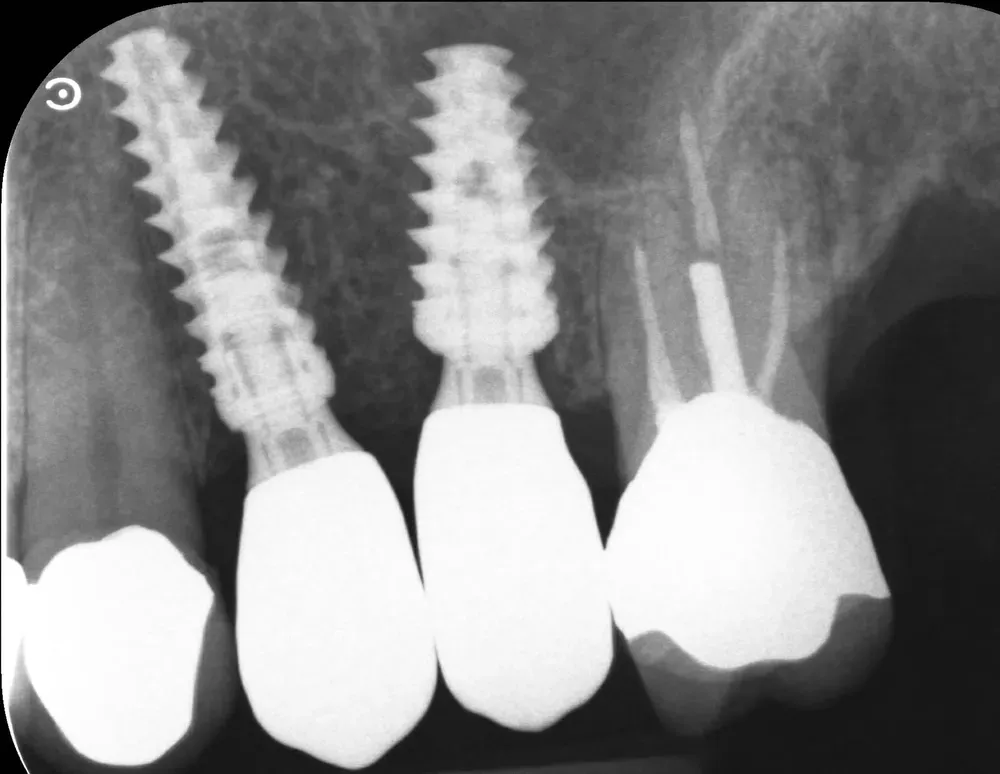

Passati tre mesi, abbiamo effettuato una scansione per realizzare le corone in zirconia. L’ultima radiografia è stata scattata il giorno della consegna delle corone.

L’aumento della densità ossea intorno all’apice dell’impianto in posizione 2.5 è evidente, particolarmente in zona mesiale. In quella zona, la corticale del seno si è sollevata maggiormente.

Rx periapicale alla consegna delle corone in zirconia